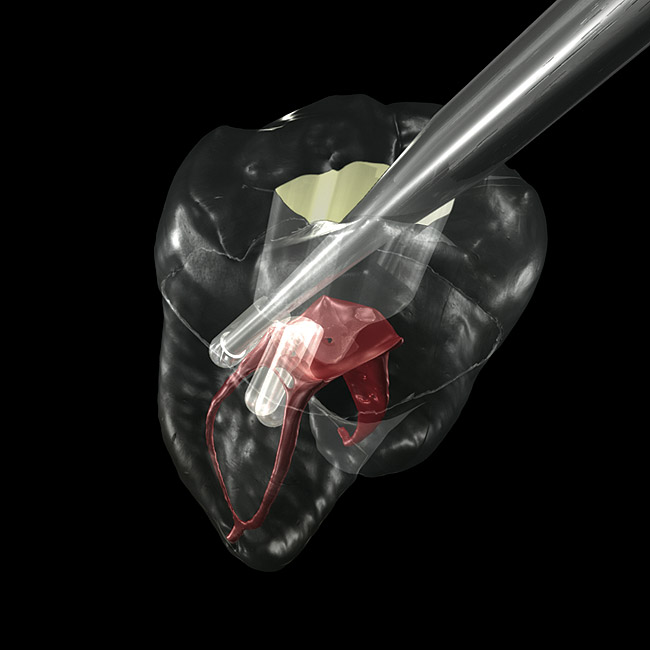

Figure 1 shows a radiograph of a typical maxillary first molar. Upon extraction, the apical anatomy was immediately studied and photographed under a global microscope ( Figure 2, Figure 3, Figure 4, Figure 5 and Figure 6). That is a take-home lesson; the extracted teeth should be studied with loupes or microscopes. These photographs demonstrate an important lesson. The two-dimensional radiograph shows three roots. In reality, however, a significant percentage of maxillary first and third molars—80% in some studies—have four roots and four or more canals. 1,2 While the MB and MP (MB-2) roots are usually fused, their morphology is unique. For diagnostic, access, and shaping purposes, it is safer to think of them as separate roots. Wisdom teeth often exaggerate the anatomic features of first and second molars, and a significant percentage of maxillary third molars have four distinct roots. The author's personal bias is to consider most maxillary first the radiographic apex of the tooth. The use of the radiographic root apex for use as the reference point for measuring the apical extent of the root filling is the common standard, yet has been criticized because of the poor correlation between the location of this point and the actual canal foramen. 5 The illustrations used in advertising and manufacturer's "tip cards" only further the notion of simple foramen anatomy. While simple anatomy is often the case with incisor teeth, a quick perusal of the posterior teeth in Brown and Herbransen's Dental Anatomy & 3D Interactive Tooth Atlas demonstrates that a significant portion of the foramen exit short of the apex and have multiple foramina. 6 The same extracted tooth in Figure 2 demonstrates that the palatal foramen is more than a millimeter short of the radiographic apex. If this tooth were filled to the constriction, which for arguments sake is 0.75 mm from the foramen, a straight-on radiograph would depict the fill as being at least 2 mm "short."